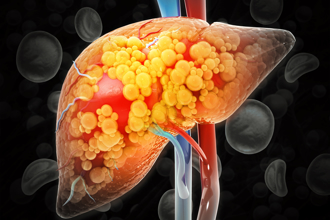

脂肪肝不理慘了!20%患者跳級惡化 醫:直接肝癌

隨著飲食西化、不健康的飲食型態增加,國人罹患脂肪肝的比例也逐年上升。醫師張振榕指出,長期忽視脂肪肝,不治療、不控制,一旦肝硬化,靜脈曲張破裂,就會大出血。此外,也有不少脂肪肝患者,會跳過肝硬化,直接得肝癌,必須有所警覺。